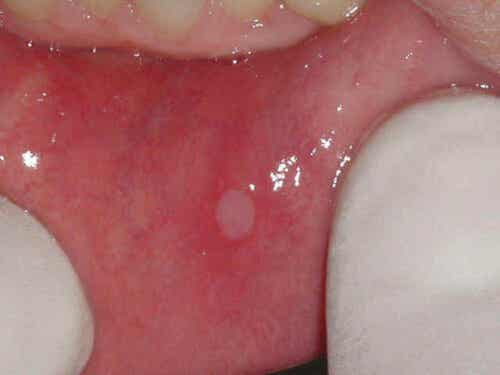

Disse lesjonene består vanligvis av en enkelt rund, hvitfarget lesjon omgitt av et betent område. De er sjelden større enn 8 millimeter.

I tillegg er det ofte mer enn ett sår, og disse er vanligvis mindre enn 3 millimeter. Det er også tilfeller der disse lesjonene er større, og helbredelsen av disse er mer kompleks.